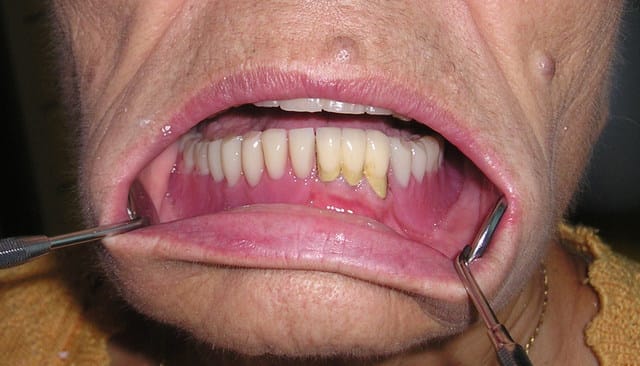

Mon premier complet immédiat sur implants fait cette semaine...

Implants posés mercredi matin, bridge posé jeudi matin...

Blague à part, son appareil à 15 ans, il veut la même chose en haut qu'en bas... pas d'os... je suis en train de me creuser la tête pour trouver une solution convenable.